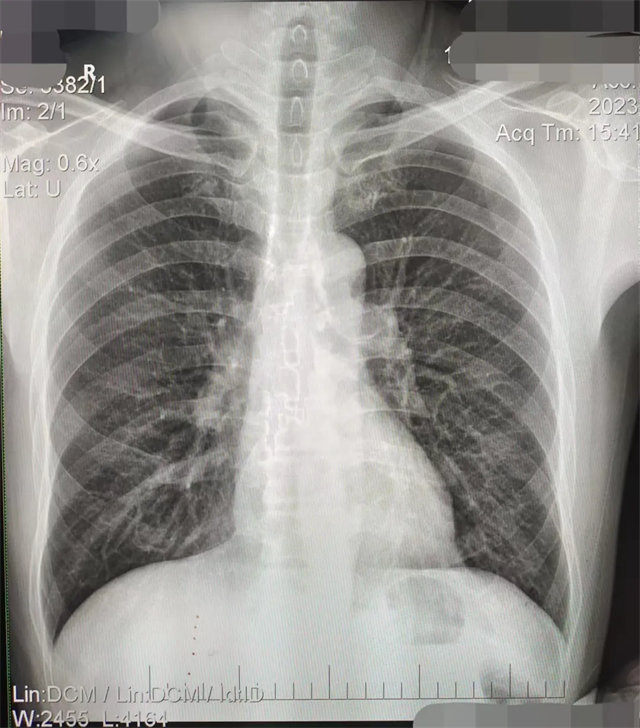

缺陷:兩肩胛骨未拉開肺野之外,吸氣不完全,且存在金屬飾品遮擋。

解決:去除金屬飾品及內(nèi)衣后重新按標(biāo)準(zhǔn)體位攝片即可。